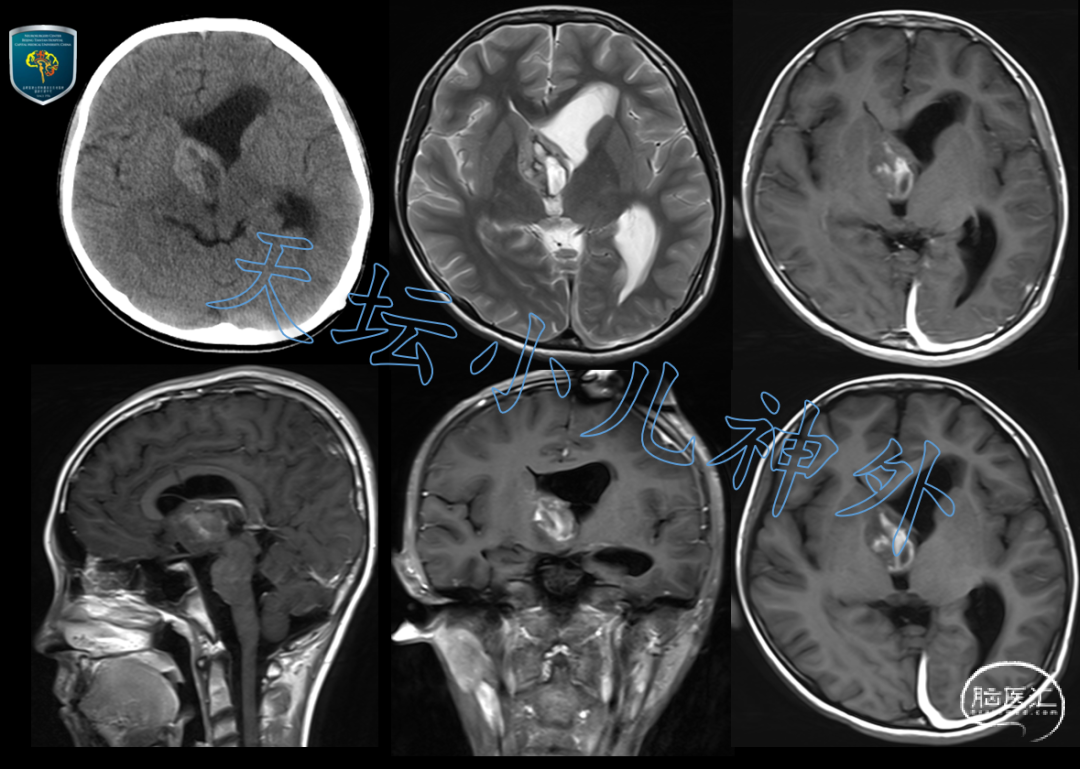

2021年8月接诊一例来自北京10岁男性患儿(身高:155cm,体重:35kg)。主诉:间断性呕吐一月,突发意识丧失外院行脑室-腹腔分流术后两周。患儿一月前晨起恶心、呕吐,持续不缓解;两周前突发抽搐伴意识丧失,外院检查发现颅内占位合并梗阻性脑积水,急行左侧脑室-腹腔分流术后意识清醒、状态明显好转,遂来我院就诊。门诊查体:神清语利、精神好,未见明显神经系统阳性体征;头颅CT示:室间孔区团块状混杂密度影,边界尚清,大小约26×26×20mm,左侧脑室明显扩张,中线结构右移;头颅MRI示:室间孔区团块状混杂信号影,部分突入第三脑室,不均匀强化,边界尚清,大小25×30×26mm,室管膜瘤?;否认多饮多尿史;血清学激素水平及肿瘤标记物均正常(图1)。

图1 术前头颅CT示:室间孔区团块状混杂密度影,边界尚清,大小约26×26×20mm,左侧脑室明显扩张,中线结构右移;头颅MRI示:室间孔区团块状混杂信号影,部分突入第三脑室,不均匀强化,边界尚清,大小25×30×26mm,室管膜瘤?